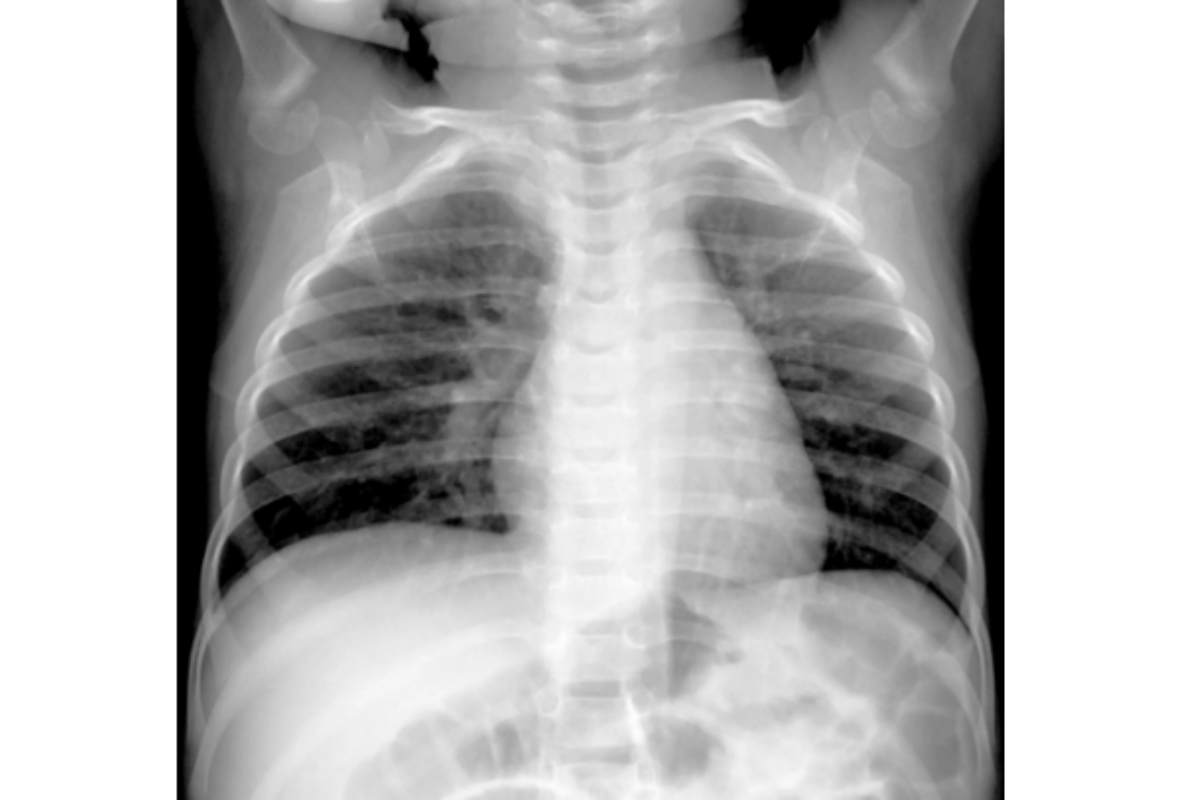

Recenti notizie su un aumento dei casi di un virus respiratorio in Cina hanno evocato ricordi del Covid-19, scoppiato quasi cinque anni fa. Tuttavia, scrive il New York Times, gli esperti rassicurano: la situazione attuale è molto diversa e meno preoccupante. Si tratta dell’HMPV (virus metapneumovirus umano), un patogeno noto che causa malattie respiratorie, già diffuso a livello globale.

L’HMPV è un virus comune che infetta la maggior parte delle persone durante l’infanzia, con possibili reinfezioni nel corso della vita. Nei paesi con climi freddi, il virus segue una stagionalità simile all’influenza, mentre nelle aree tropicali circola tutto l’anno a livelli inferiori. I sintomi includono tosse, febbre, congestione nasale e respiro affannoso, simili a quelli dell’influenza o del Covid-19. Sebbene la maggior parte delle infezioni sia lieve, casi gravi possono colpire neonati, anziani e persone con sistema immunitario compromesso.

L’HMPV si trasmette attraverso goccioline o aerosol da tosse e starnuti, contatto diretto o superfici contaminate, come accade per il raffreddore o l’influenza. Al momento, non esistono vaccini o trattamenti specifici contro il virus, ma si stanno studiando soluzioni combinate con il vaccino per l’RSV, un virus simile.